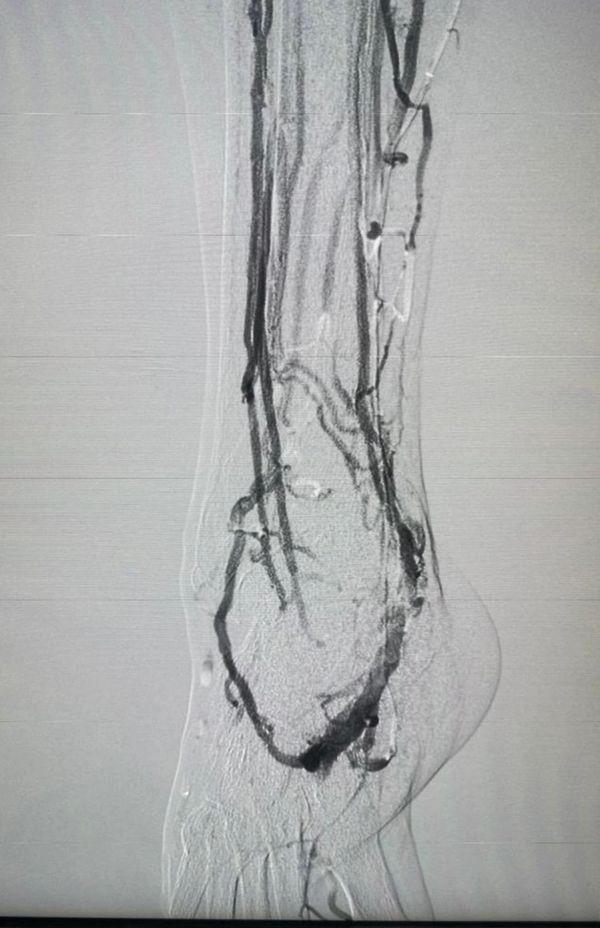

Angiólogos certificados, especialistas en el tratamiento de mínima invasión de la enfermedad venosa crónica (Várices ) , fleboestética , salvamento del pie diabético, manejo avanzado de heridas crónicas, Aneurismas , Fístulas Arteriovenosas y todo lo relacionado a los problemas de la circulación.